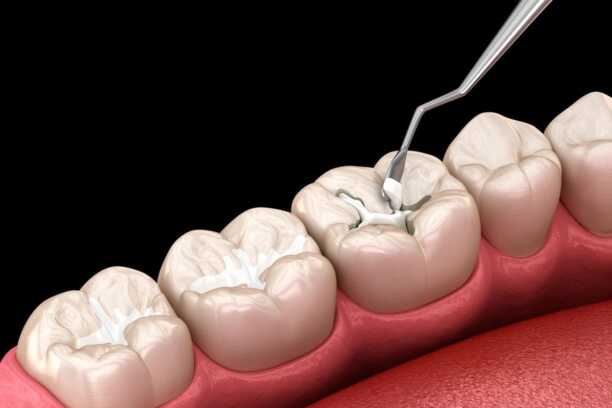

خطوات حشو الأسنان

- الفحص السريري وتقييم حالة السن

- أخذ الأشعة لتحديد عمق التسوس

- إزالة الجزء المصاب بدقة

- تنظيف التجويف وتعقيمه

- وضع مادة الحشو المناسبة

- تشكيل الحشو ليتوافق مع شكل السن الطبيعي

- تلميع الحشوة لضمان الراحة أثناء المضغ

كل خطوة من هذه الخطوات تساهم في تحقيق نتيجة مثالية، ويظهر الفرق جليًا عند مقارنة حشو اسنان قبل وبعد.